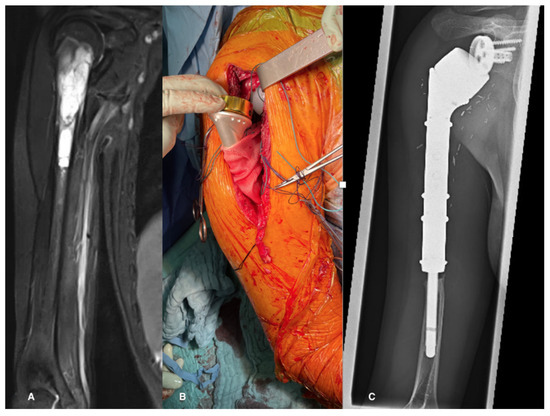

To enhance joint stability and facilitate active function through the reattachment of soft tissues to the implant—notably the deltoid, latissimus dorsi, subscapularis, and pectoralis muscles—an attachment tube was employed for all patients during surgery. Subsequently, the shoulder was immobilized in a sling with an abduction pillow for a duration of four to six weeks, contingent upon the extent of soft tissue reconstruction (Figure 2).

3.7. Longer-Term Follow-Up

A subset of 26 patients had follow-up durations exceeding 24 months, with a median follow-up duration of 66 months (range: 24–176 months) (Figure 2C and Figure 4). During this extended follow-up period, one patient experienced infection, while four patients encountered dislocations. Importantly, the dislocations of the humeral implant occurred exclusively during the first year post-surgery. Following repositioning and conservative treatment, all patients regained function. In one case, the polyethylene liner had to be replaced nine years after the initial implantation due to perceived instability. Subsequent revision surgery successfully restored the range of motion to previous levels. At the latest follow-up, radiological assessments showed no signs of humeral or glenoid component loosening. Nevertheless, in 62% of the patients, stress shielding was seen, but so far, complications due to the stress shielding has not occurred.

Figure 2. (A) MRI showing a Ewing’s sarcoma in a 13-year-old patient, (B) intraoperatively after reconstruction with an inverse tumor prosthesis and an attachment tube, (C) the 7-year follow-up X-ray shows, besides stress shielding, no signs of implant complications.